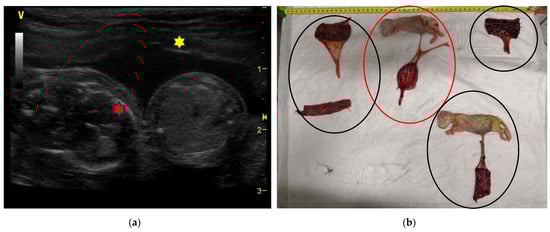

| 1F 2F | 6-year-old Birman female cat | 45 and 52 | 5 | Two pairs of monochorionic twins, morphologically comparable to the other foetus. | Natural delivery without assistance, three kitten stillborn. | One kitten dead for sepsis after 7 days. |

| 3F | 4-year-old European female cat | 50 | 4 | Monochorionic twins, morphologically comparable to the other foetuses. | Natural delivery without assistance, entangled neonates’ umbilical cords. | |